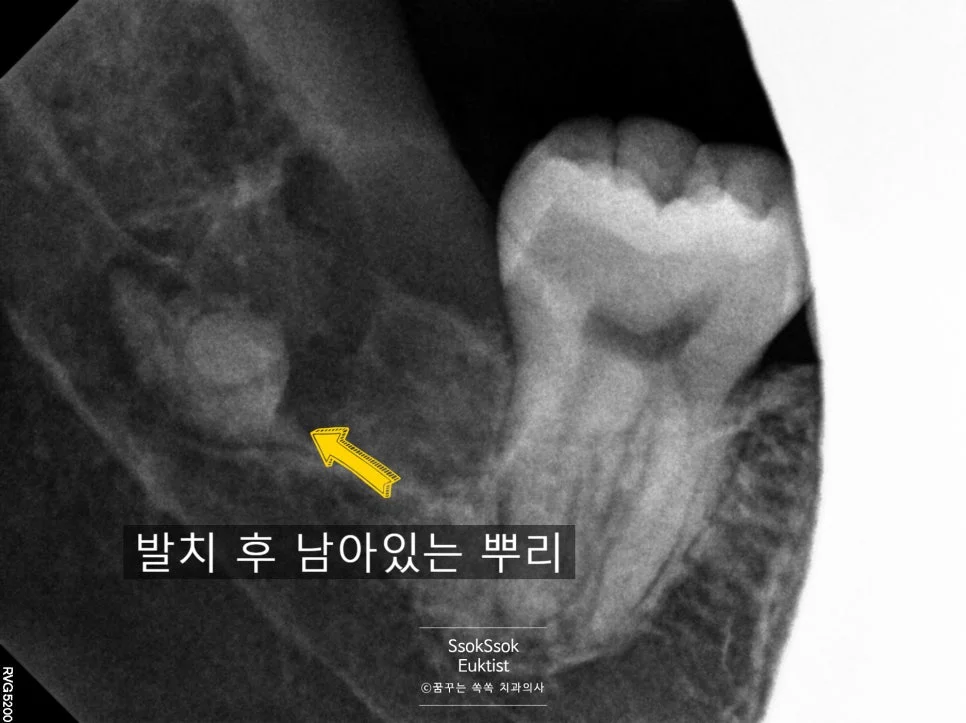

사랑니 뿌리가 서로 다른 방향으로 휘어 있는 구조

뿌리가 서로 다른 방향으로 휘어 있어 한 번에 나올 수 없는 상황인데요. 이런 경우 뿌리가 전부 나오지 않고 뿌리의 조각이 일부 남아 있게 될 수 있습니다.

역시나 아래쪽 뿌리 일부가 남게 된 상태

역시나 아래쪽 뿌리 일부가 남게 되었는데요. 여기서 두 가지 선택지가 있습니다.